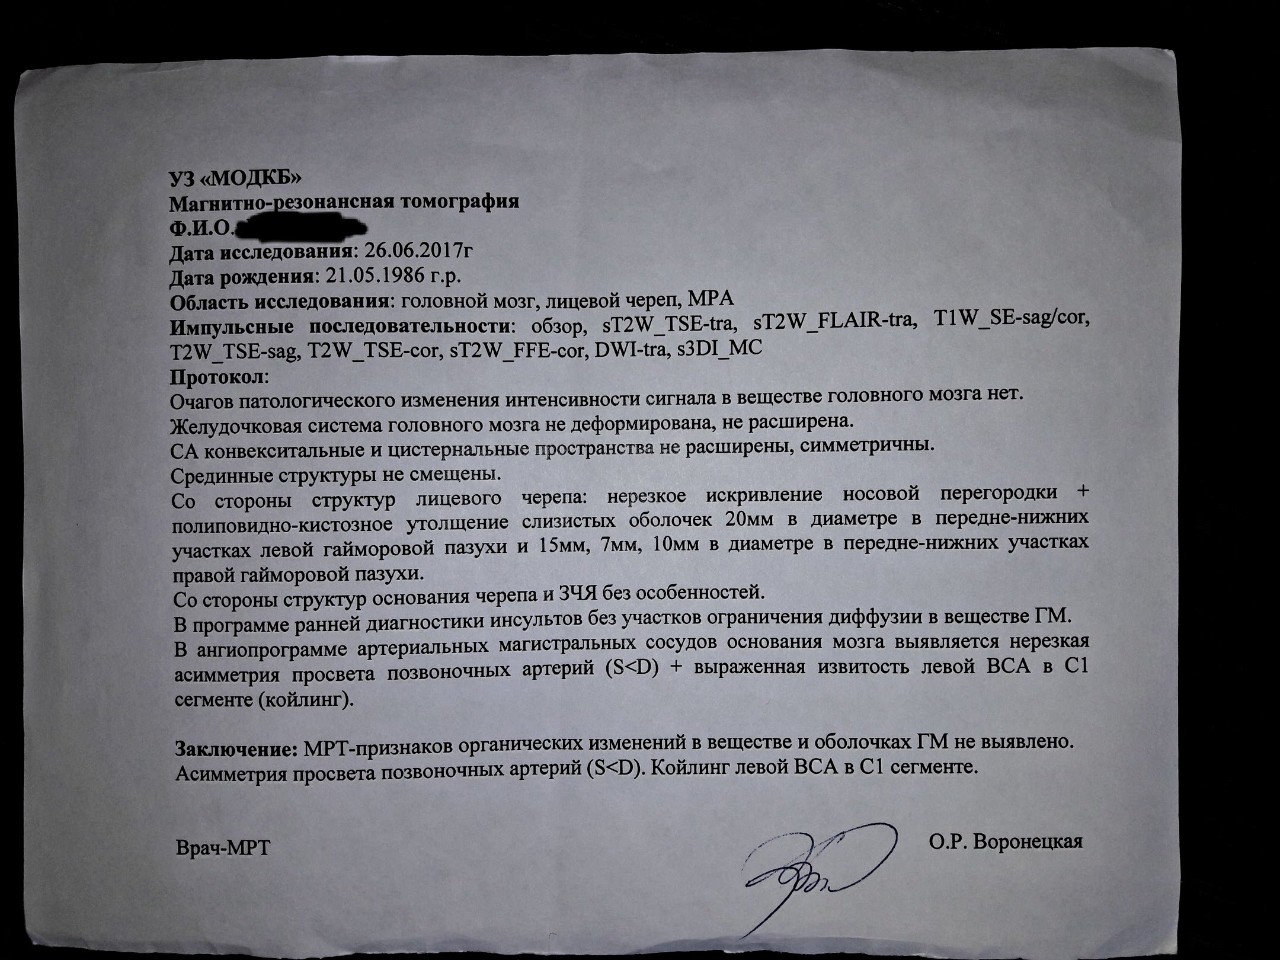

МРТ головного мозга: Расшифровка снимков и Интерпретация

Раздел: Визуальные уроки